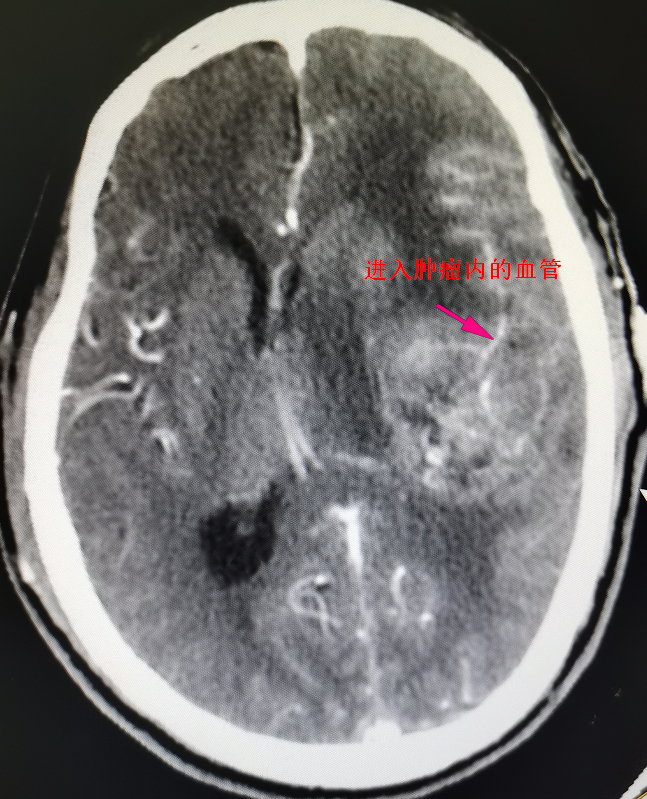

62岁的陈先生于今年曾因偏瘫在外院住院治疗无好转,且症状不断加重,甚至出现言语不清,小便失禁等异常。经影像检查(见图1)提示为左颞叶基底节区脑肿瘤,约6cm*5cm*5cm大小,比鹅蛋还要大,肿瘤位置深,向前累及外侧裂,包裹外侧裂部分血管,向下累及基底节区,肿瘤血供丰富,必须尽早实施手术治疗。

术前影像资料及手术标本,术前见中线结构严重偏移,侧脑室受压缩小,肿瘤周围水肿严重,肿瘤血供丰富

“由于肿瘤的位置侵犯外侧裂,影像学确定肿瘤包裹外侧裂的分支血管,有大脑中动脉以及枕动脉的多分支供血,紧邻肿瘤的还有过路血管。被包裹大的过路血管是不能损伤的,术中不小心损伤这段血管的话,大脑就会出现梗塞等一系列的并发症。”刘建民表示。